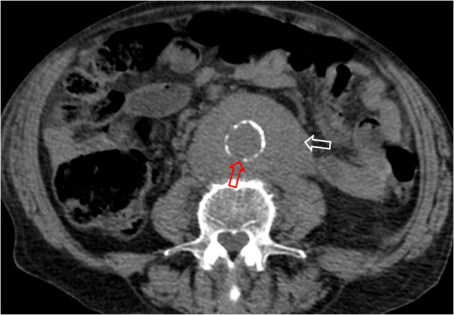

SIGNO DE LA AORTA PEQUEÑA

Signo de hipovolemia en la TC abdominal. Corresponde a vasoconstricción extrema de la aorta (flecha roja) como mecanismo que trata de compensar la hipovolemia que se ve en pacientes politraumatizados con grandes pérdidas hemáticas y en otras situaciones (shock séptico, cirugía, parada cardiaca, reacción alérgica,…). Se define como un calibre aórtico menor de 1,3 cm tanto dos centímetros por encima de las arterias renales como 2 cm por debajo. El ejemplo corresponde a un paciente politraumatizado con un bazo roto (flecha blanca).

Este signo forma parte del complejo de hipotensión en CT, antes llamado shock intestinal. Este término se refiere a un grupo de hallazgos abdominales en pacientes con hipotensión severa. Incluye: engrosamiento de asas de delgado (> 3 mm), realce de las paredes o hiperdensidad comparada con el psoas, vena cava inferior plana, aorta pequeña, heterogenicidad del páncreas con líquido peripancreático (no unánimemente aceptado), escaso realce del bazo (subjetivo), escaso realce hepático (25 UH menor que el bazo) e hiperrealce suprarrenal bilateral (hallazgo común en niños, controvertido en adultos).

Otro ejemplo de aorta pequeña en otro politraumatismo. El contraste se introdujo por una vía femoral, de ahí el intenso relleno de la vena cava inferior.